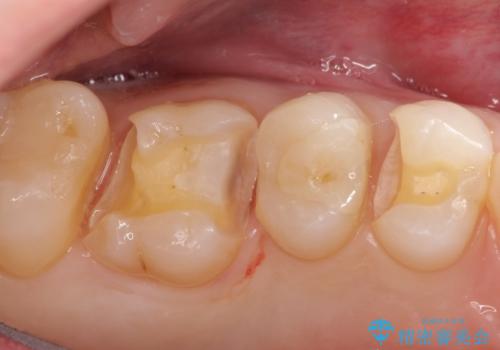

- 金属のインレーを除去を希望されて来院されました。

セラミックインレーにて治療を行なっております。

e-max プレスインレーにて修復治療を行っているため適合性及び審美性の高い治療を行うことができます